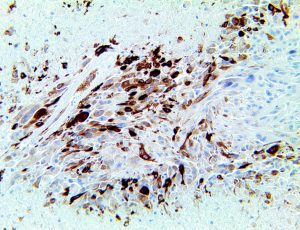

It is the ICU physician who is most likely to witness one of the deadliest manifestations of the abnormal immunological response, the cytokine storm syndrome (CSS). This response is also referred to by some as the cytokine release syndrome (CRS). CSS is characterized by continuous activation and expansion of macrophage and lymphocyte populations, which secrete large amounts of cytokines, causing the cytokine storm. This massive cytokine release is akin to hemophagocytic lymphohistiocytosis (HLH) disease, a syndrome characterized by initial unchecked and persistent activation of cytotoxic T lymphocytes and NK cells.

Clinical and laboratory manifestations of HLH include fever, enlarged liver and/or spleen, neurologic dysfunction, coagulopathy, liver dysfunction, cytopenias (i.e., low levels of erythrocytes, leukocytes, and/or platelets), hypertriglyceridemia, hyperferritinemia, hemophagocytosis, and eventually diminished NK cell activity as the immune system becomes progressively paralyzed. HLH can be familial (primary HLH) or secondary to another disease process (sHLH), such as rheumatic disease, in which it is referred to as macrophage activation syndrome (MAS, characterized by elevated ferritin).